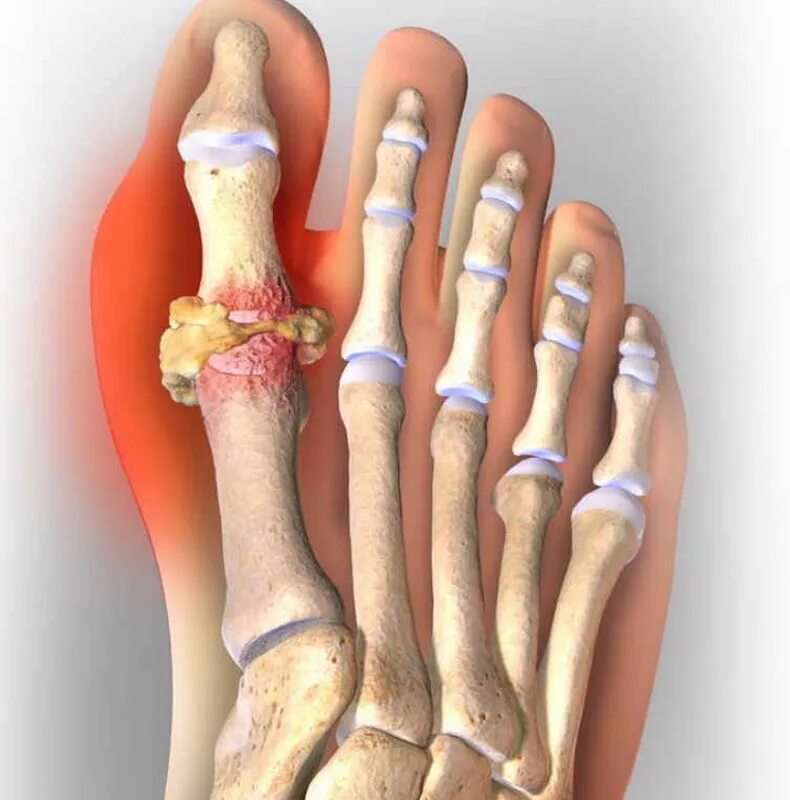

Подагра суставов стопы